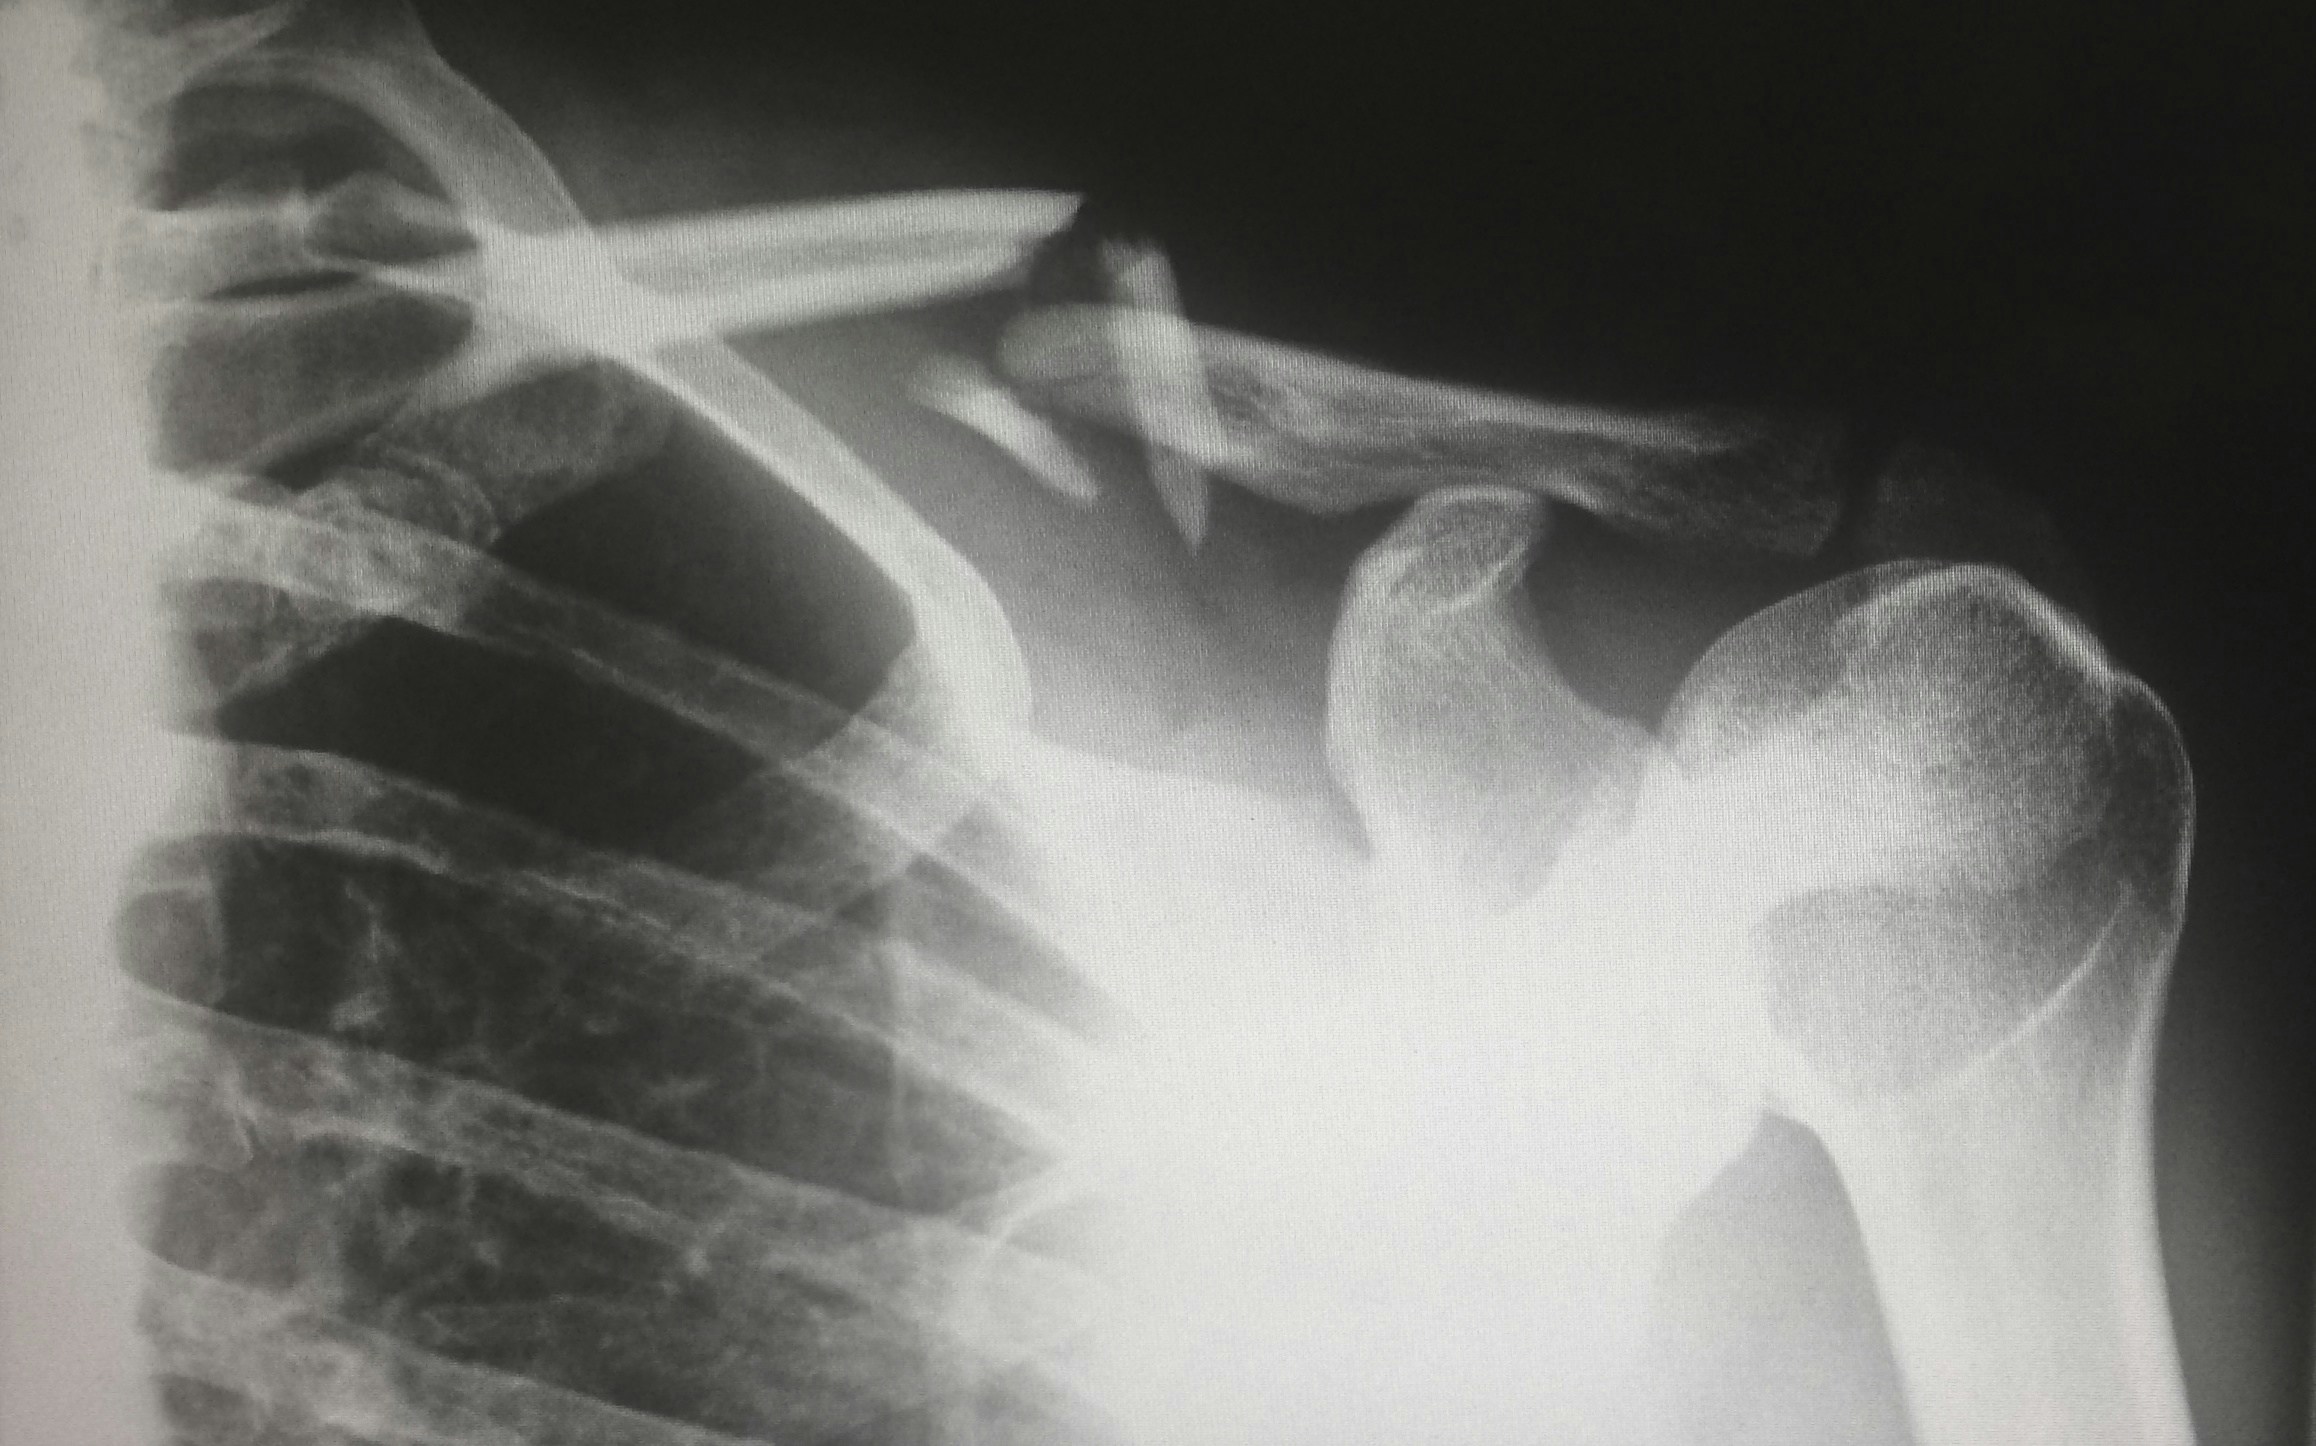

Light conversion technology developed by University of Queensland researchers will be used for wearable X-ray devices that make respiratory scans more comfortable for children. Associate Professor Jingwei Hou from UQ’s School of Chemical Engineering was tasked to produce a flexible, glass-based X-ray imaging detector that can be worn in a hoodie or blanket to provide a quick and accurate picture of a child’s lungs.

Associate Professor Jingwei Hou from UQ’s School of Chemical Engineering has been awarded an Investigator grant from the National Health and Medical Research Council (NHMRC) to produce a flexible, glass-based X-ray imaging detector that can be worn in a hoodie or blanket to provide a quick and accurate picture of a child’s lungs.

But he said current X-ray technology merely captures a flat projection of a 3D object, meaning numerous scans from different angles are required to render computed tomography (CT) results, potentially leading to high radiation exposure.

To solve the issue, Dr Hou will adapt his patented quantum dot hybrid glass technology into thin film strips that that conform to the contour and movement of a child’s body and can be worn like a favourite blanket or jumper.

“By assembling these materials into thin, flexible X-ray detectors I can create a wearable X-ray detector that is both comfortable while still providing high-resolution imaging of lung structure.”